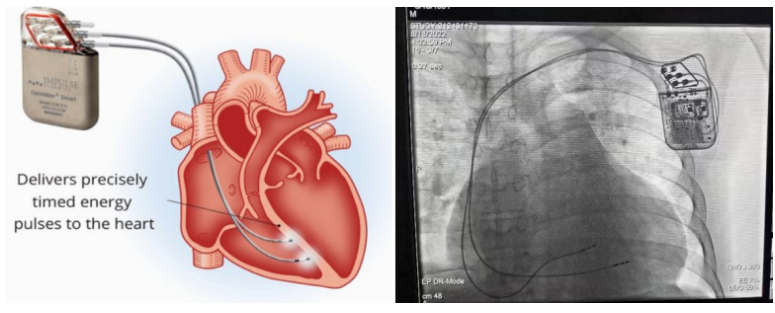

①植入式心臟復(fù)律除顫器

Implantable Cardioverter Defibrillator,ICD

植入式心臟復(fù)律除顫器是一種具有除顫功能的高級(jí)起搏器,是一種體積小、能植入患者胸部皮下組織的醫(yī)療設(shè)備。慢性心衰患者易發(fā)生室性心動(dòng)過(guò)速或心室顫動(dòng),導(dǎo)致心源性猝死(SCD)。ICD 則能在幾秒內(nèi)自動(dòng)識(shí)別并治療快速室性心律失常,通過(guò)低能量心臟轉(zhuǎn)復(fù)和高能量除顫等功能,顯著降低惡性室性心律失常引起的猝死風(fēng)險(xiǎn)??杉皶r(shí)自動(dòng)為患者轉(zhuǎn)復(fù)心律,通俗地說(shuō)就是裝在體內(nèi)的自動(dòng)除顫儀。

國(guó)內(nèi)研發(fā)企業(yè):無(wú)雙醫(yī)療、邁瑞、魚(yú)躍、久心、微創(chuàng)、維偉思、麥邦等

②心臟再同步治療

Cardiac Resynchronization Therapy,CRT

心臟再同步化治療,指雙心室起搏器,是通過(guò)雙心室同步起搏的方式,幫助心衰患者實(shí)現(xiàn)正常起搏的裝置。CRT包括一個(gè)口袋大小的脈沖發(fā)生器和三根電極導(dǎo)線,可被植入人體。通過(guò)監(jiān)測(cè)心律,在發(fā)現(xiàn)異常后,信號(hào)發(fā)生器發(fā)送電流脈沖,刺激心室重新同步,從而改善癥狀,提高患者的心臟泵血效率。目前有兩種類型的CRT裝置:植入式心臟再同步治療起搏器(CRT-P)和植入式心臟再同步治療除顫器(CRT-D)。主要區(qū)別在于后者除了改善心臟收縮同步性外,還具備除顫功能,能及時(shí)處理危及生命的室性心律失常,避免猝死。

國(guó)內(nèi)研發(fā)企業(yè):無(wú)雙醫(yī)療、樂(lè)普醫(yī)療、先健科技、創(chuàng)領(lǐng)心律、秦明醫(yī)學(xué)等